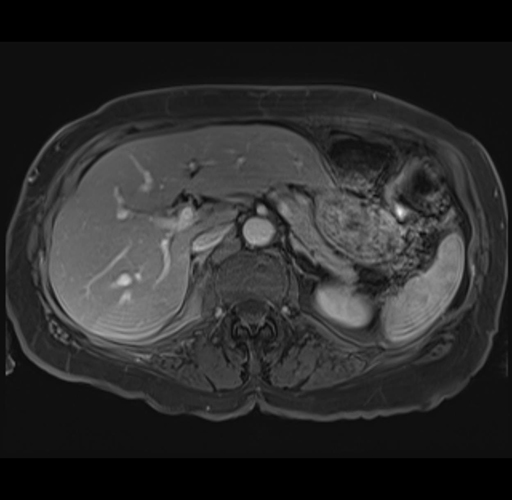

MRI T1